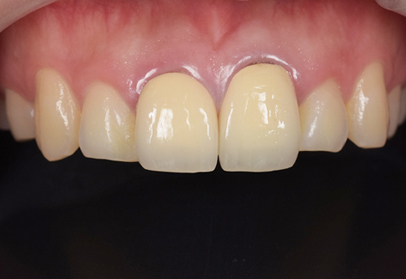

初診時

初診時、前歯の角度はかなり前に向かって生えています。この状態から神経の治療を行うことなく、かぶせ物で角度を変えるのは、限界があるとお伝えして、神経の治療をまず行なってから、歯を削って仮歯を入れる治療計画を伝えて行なった。

セラミックセット時

初めに仮歯に置き換えてから問題なければ、仮歯を最終的な形のプロビに置き換えます。プロビにて歯肉とのマッチングや形や出具合を確認してもらい約1ヶ月の期間使用してもらいます。問題がなければ、最終的な型採りを行い、セラミックの試適、そして完成となりました。